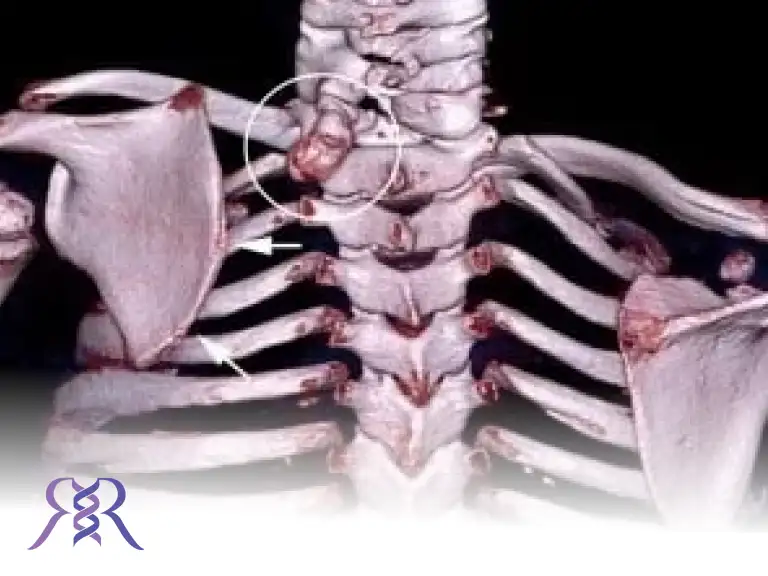

سیتیاسکن (CT Scan): جزئیات دقیقتری از شکل استخوان، میزان بدشکلی و ارتباط کتف با ساختارهای اطراف نشان میدهد.

از نظر پاتوفیزیولوژی، علاوه بر تغییر مکان کتف، اغلب یک باند فیبروزی یا استخوانی غیرطبیعی (اوموورتبرال باند – Omovertebral band) بین کتف و ستون فقرات گردنی یا فوقانی وجود دارد. این باند همانند یک اتصال غیرطبیعی عمل کرده و مانع حرکت آزاد کتف میشود. همچنین در برخی موارد، همراهی با سایر ناهنجاریهای مادرزادی مثل اسکولیوز، ناهنجاریهای مهرهای یا سندرم کلاینفلتر مشاهده شده است.

در بسیاری از موارد، یک نوار استخوانی یا فیبری غیرعادی به نام اوموورتبرال باند (omovertebral bar) استخوان کتف را به ستون مهرهها متصل میکند. این ساختار میتواند دامنه حرکت شانه را بهشدت محدود کرده و مانع عملکرد طبیعی عضلات اطراف شانه شود.